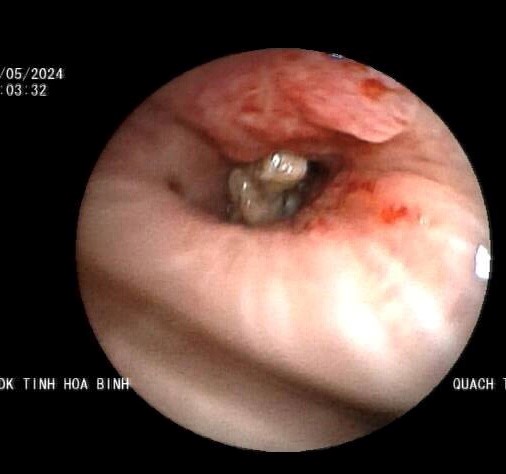

Tại Bệnh viện Đa khoa tỉnh Hoà Bình, bệnh nhân được hội chẩn các chuyên khoa: Hồi sức tích cực, Hô hấp, Gây mê hồi sức, Chẩn đoán hình ảnh. Các thầy thuốc đã tiến hành nội soi phế quản ống mềm có gây mê để khảo sát toàn bộ đường thở của bệnh nhân. Khi đưa ống nội soi đến phế quản thuỳ dưới phổi trái, phát hiện một dị vật to bằng đầu ngón tay út, có nhiều góc cạnh, có đờm và mủ bao phủ bên ngoài. Dị vật chắn ngang phế quản làm cản trở thông khí của thuỳ dưới phổi trái, kèm theo đó là tình trạng hoá mủ và áp xe hoá thuỳ dưới phổi trái. Ngoài ra, di vật di động theo nhịp thở, cọ vào thành phế quản gây chảy máu trong lòng phế quản.

Dị vật nằm trong phổi bệnh nhân ở phế quản thuỳ đưới phổi trái